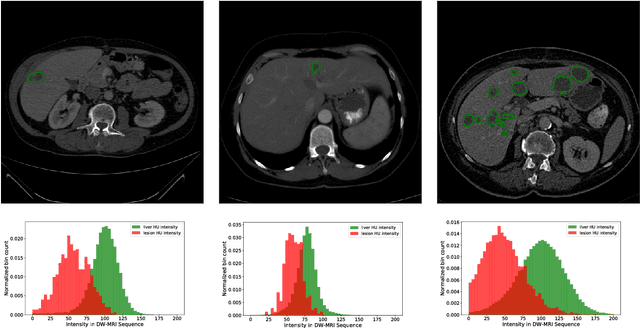

Abstract:In this work, we report the set-up and results of the Liver Tumor Segmentation Benchmark (LITS) organized in conjunction with the IEEE International Symposium on Biomedical Imaging (ISBI) 2016 and International Conference On Medical Image Computing Computer Assisted Intervention (MICCAI) 2017. Twenty four valid state-of-the-art liver and liver tumor segmentation algorithms were applied to a set of 131 computed tomography (CT) volumes with different types of tumor contrast levels (hyper-/hypo-intense), abnormalities in tissues (metastasectomie) size and varying amount of lesions. The submitted algorithms have been tested on 70 undisclosed volumes. The dataset is created in collaboration with seven hospitals and research institutions and manually reviewed by independent three radiologists. We found that not a single algorithm performed best for liver and tumors. The best liver segmentation algorithm achieved a Dice score of 0.96(MICCAI) whereas for tumor segmentation the best algorithm evaluated at 0.67(ISBI) and 0.70(MICCAI). The LITS image data and manual annotations continue to be publicly available through an online evaluation system as an ongoing benchmarking resource.